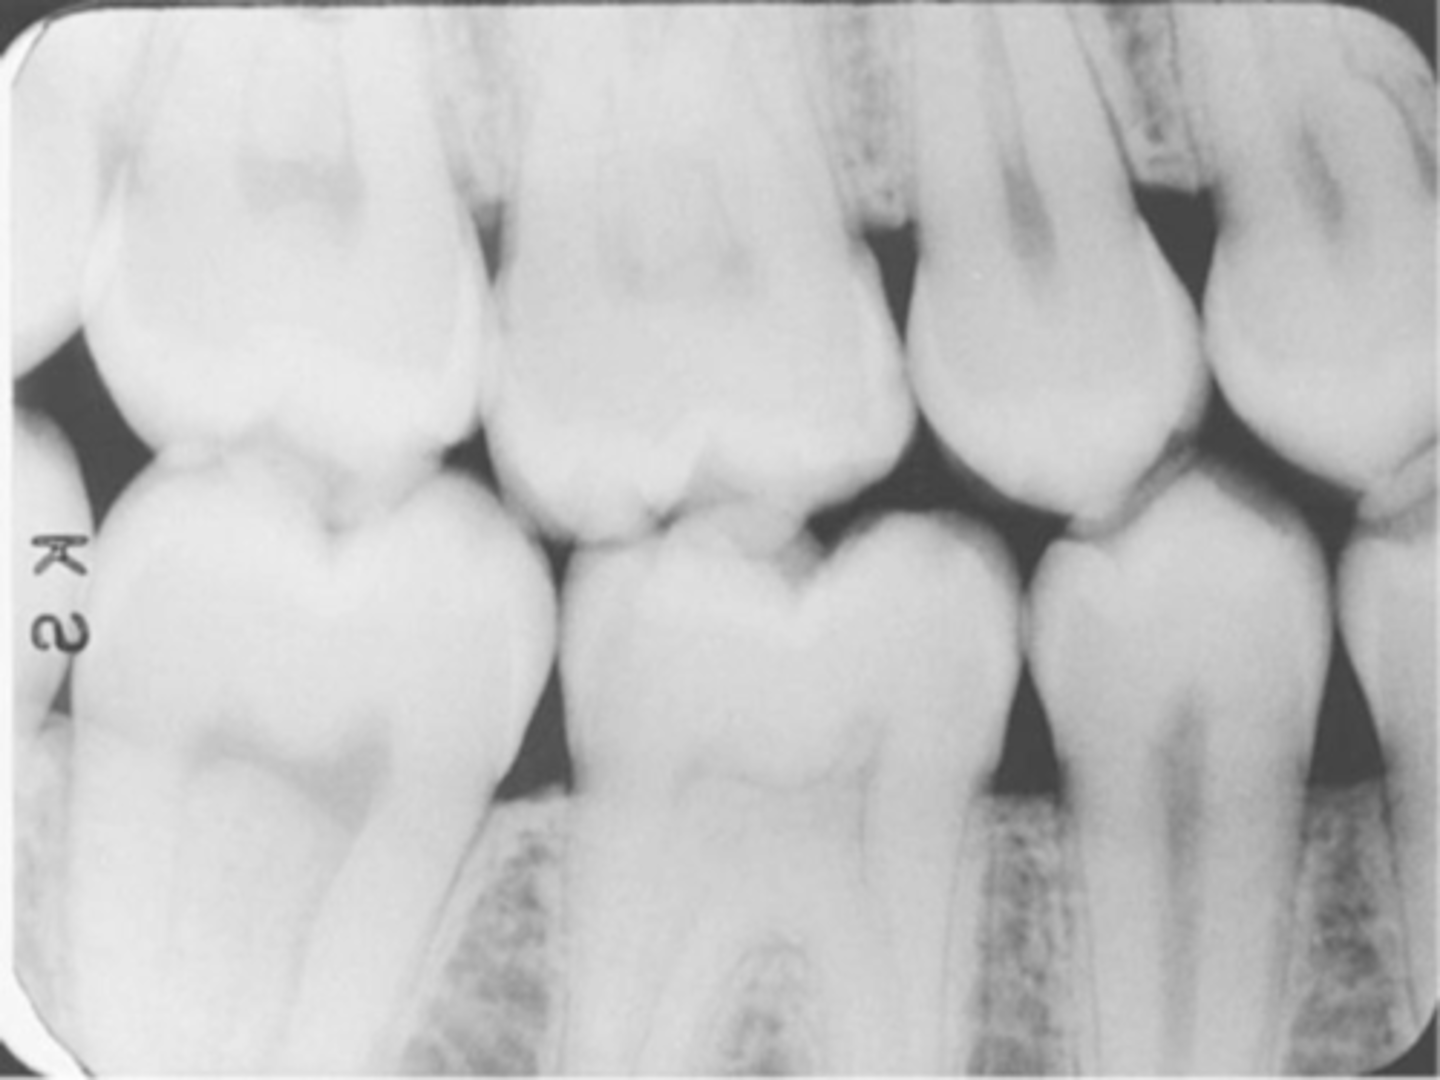

overlapped contacts

contacts are overlapped

central ray not directly through the interproximal spaces